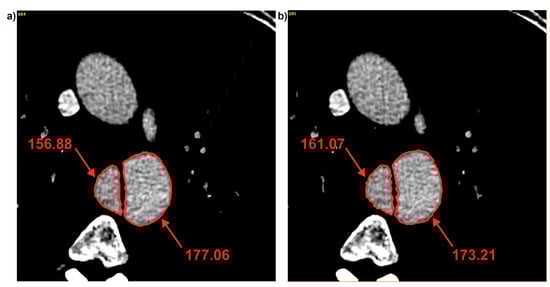

3.2. Brightness Value Analysis

| Patient | Average Brightness | ||

|---|---|---|---|

| Common | True | False | |

| Pat I | 184.73 ± 16.75 | 141.36 ± 20.26 | 178.01 ± 6.04 |

| Pat II | 331.11 ± 18.41 | 364.03 ± 14.10 | 320.10 ± 12.60 |

| Pat III | 291.13 ± 6.60 | 213.52 ± 39.70 | 313.91 ± 8.62 |